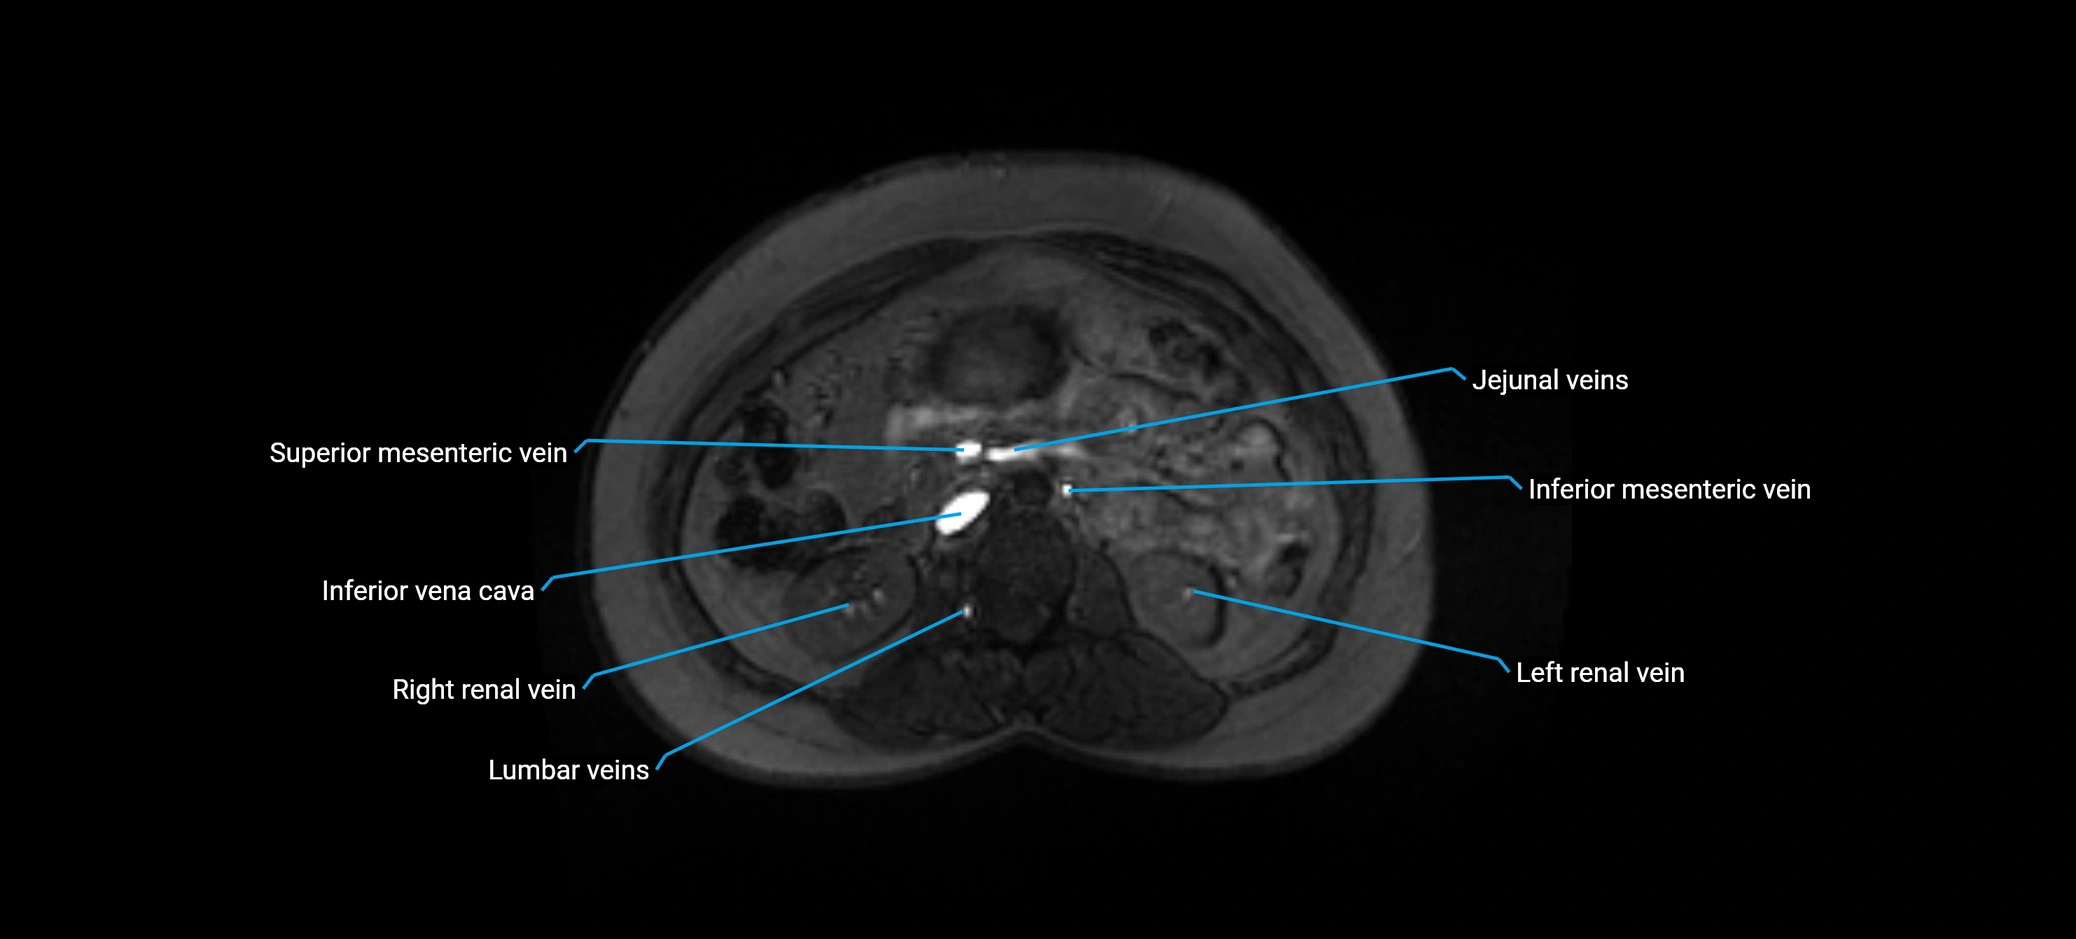

MRI image

image